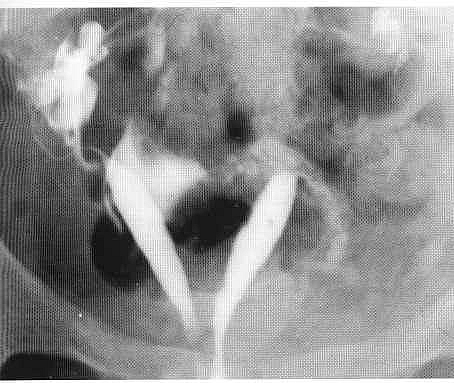

The procedure involves the instillation of a radio-opaque dye, through a small catheter placed in the cervical canal, into the uterine cavity. The X-ray image obtained shows the uterine cavity, the outline of the Fallopian tubes and the presence or absence of dye in the abdominal cavity.When dye is seen to flow freely into the abdominal cavity, tubal patency is confirmed. However, if the dye spill appears to be loculated or the tube appears to be in an abnormal position, peri-tubal adhesions are likely to be present: Uterine adhesions and submucous fibroids appear as filling.Defects on the X-ray image and require further assessment by hysteroscopy.